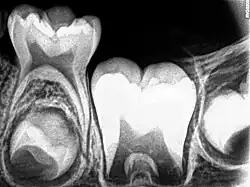

Radiograph of lower right (from left to right) third, second, and first molars in different stages of development

X-ray of teeth of a boy aged 5 years showing left lower primary molar and developing crowns of left lower permanent premolar (below primary molar) and permanent molars